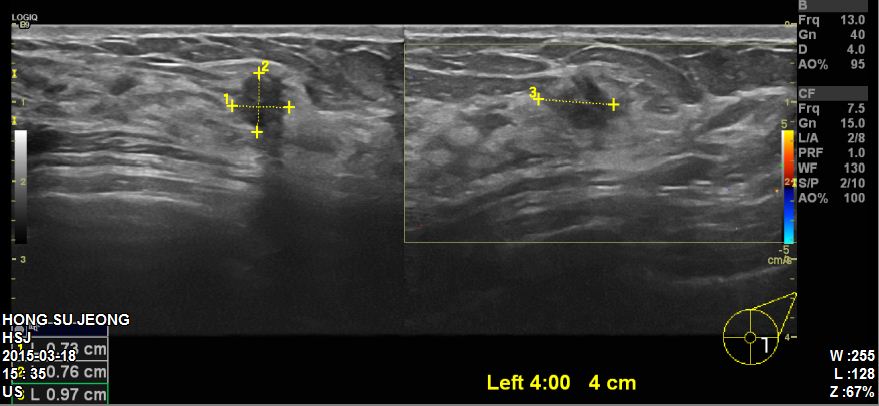

본원에 내원하신 60대 환자분이십니다.

유방초음파 시행후 좌측 4 : 00 방향에 혹 조직검사 시행하였고

침윤성유관암 진단되었습니다.